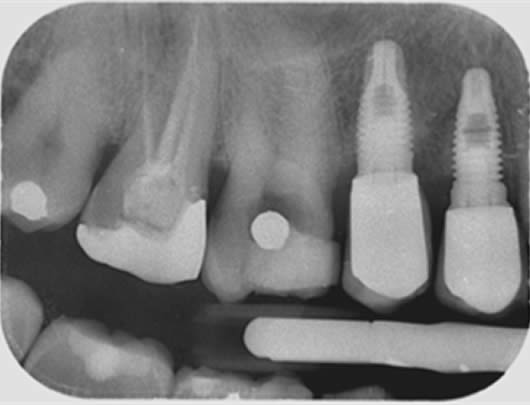

Case 2: Root canal treatment – the elusive MB2 canal.

In approximately 90% of upper first molars there are four root canals. The fourth canal (MB2) is difficult to locate and can be very challenging to negotiate to its end. It is a very common occurrence that this canal is missed during treatment and this can lead to failure. We use a dental microscope, which magnifies the tooth and assists us in locating this canal. We then use a series of tiny instruments in a specific technique, honed over many hours of practice, to negotiate to the end of the canal. This case shows the filling of all four canals.

Pre-operative radiograph UR6

Post-operative radiograph UR6